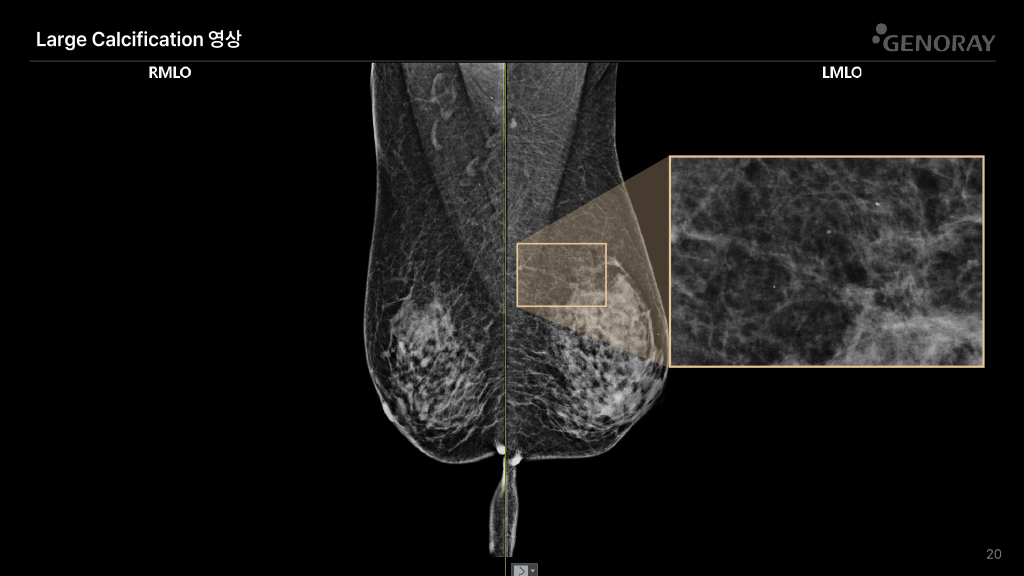

CLINICAL IMAGES

오랜 경험을 통해 축적된 노하우로 진단영상을 제공합니다.